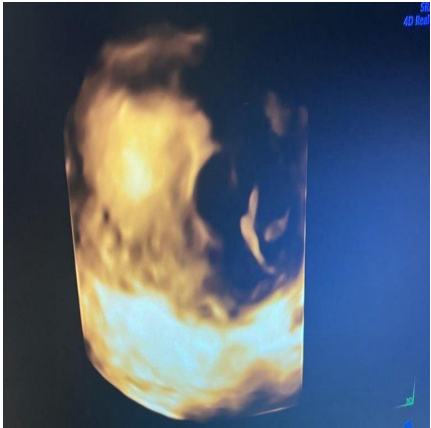

A 16-year-old lady, para 0+2 presented to the emergency department complaining of active vaginal bleeding after medical treatment of missed miscarriage. She had history of two recurrent miscarriages treated by surgical evacuation. Her pregnancy was spontaneous. Her medical history was unremarkable. Clinically she was vitally stable, soft abdomen, no tenderness no palpable masses. Speculum examination was suggestive of normal-looking cervix with bleeding from the os, uniformly enlarged 8 weeks size uterus freely mobile, no cervical movement tenderness, and no adnexal masses. An ultrasound demonstrated a gestational sac about 2.2 cm in diameter. It showed also a yolk sac and a fetal pole of 8 mm without cardiac cavity. Surgical suction and evacuation was performed under ultrasound guidance.  During the evacuation, the gestational sac was noted to be below the suction tube, the procedure was aborted. The intrauterine products were sent for histology which showed fragments of endometrium, blood clots and fibrosed chorionic villi, no evidence of malignancy. Upon reassessment, she was still complaining of the vaginal bleeding. Beta human chorionic gonadotropin was 1450. A Trans abdominal & trans vaginal ultrasound scan showed empty cavity with thick endometrium, a gestational sac below the line of endometrium with a yolk sac and fetal pole without cardiac activity, embedded in the myometrium (Fig.1&2&3&4) .The use of 3-D ultrasound helped in confirming the diagnosis of intramyometrial pregnancy, providing highly informative and detailed imaging to support accurate clinical assessment (Fig.5&6). In view of her parity and future fertility medical treatment was discussed with and accepted by the patient. Methotrexate was administered with a single dose of 50mg given intramuscularly on day 7, the drop was less than 15%. The patient received a second dose of methotrexate .The patient was displaced due to war circumstances. She then continued to have serial pregnancy tests, not able to have quantitative B-HCG test. Her pregnancy test became negative eventually then her menstrual cycle resumed back with regular intervals.

FIG.5

FIG.6

Figure 5

Figure 6